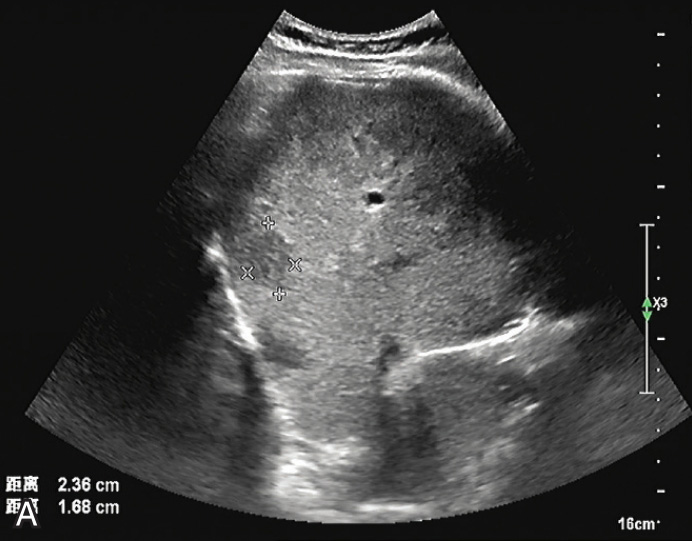

图1-5-1 肝细胞腺瘤常规超声图像

A.肝左外叶低回声结节,内可见条索状稍高回声,边界清晰;B.CDFI示其内可见点状血流信号

较小的腺瘤为较均匀或不均匀的低或稍高回声,较大的腺瘤内常伴出血、坏死和液化,瘤体内出现不规则高回声、无回声区,构成混合回声结构(图1-5-1A)。